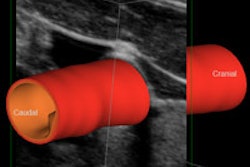

The Acuson X700 shared-service scanner is getting a new version 2.0 release of software, including the company's SieTouch elasticity imaging protocol for noninvasive analysis of relative tissue stiffness. Other enhancements include automated follicle measurements, a new high-resolution linear transducer, and better image quality for breast and small-parts imaging. Release 2.0 is currently shipping.